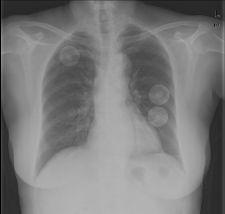

Created as a CAD solution for chest CR/DR, the IQQA-Chest Enterprise gives users a set of real-time interactive tools to support radiologists in their identification, confirmation and quantification of lung nodules as small as 5mm in diameter.